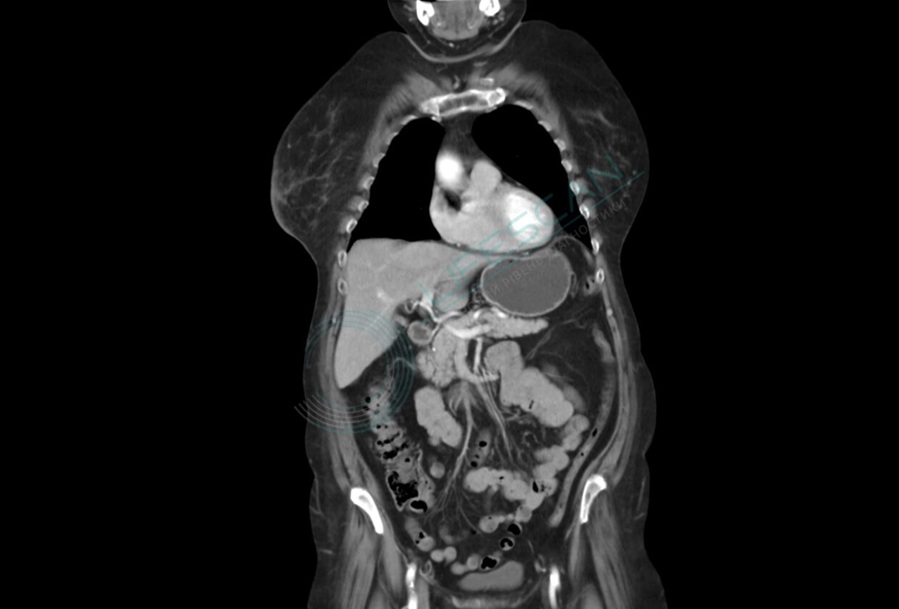

На снимках КТ человеческое тело представлено в виде последовательных срезов, отображающих внутреннюю анатомию с высокой степенью детализации. В отличие от обычного рентгена, КТ позволяет различать плотность различных тканей, благодаря чему можно четко увидеть органы, сосуды, кости и даже небольшие образования, находящиеся в толще мягких тканей. Анатомическое изображение строится по слоям – от головы до таза, в зависимости от охвата исследования. Каждый слой может быть представлен в разных проекциях: поперечной, сагиттальной и фронтальной, что обеспечивает трехмерное восприятие структуры тела.

Кости на КТ выглядят как плотные светлые структуры, мягкие ткани – как более темные участки с вариативной плотностью. Органы, такие как печень, почки, легкие и селезенка, хорошо визуализируются и оцениваются по форме, размерам, структуре и наличию патологических изменений. Легкие, из-за содержащегося в них воздуха, кажутся наиболее темными, тогда как плотные образования – наоборот, белыми. При использовании контрастного вещества сосуды становятся отчетливо видны, что позволяет проследить кровоток и выявить сосудистые патологии.

КТ особенно полезна для изучения областей, недоступных при обычной пальпации или визуальном осмотре, например, органов брюшной полости, грудной клетки и таза. Отдельно стоит отметить головной мозг и позвоночник: на КТ хорошо различимы структуры черепа, мозговые желудочки, отеки, кровоизлияния, а также костные элементы позвоночника и межпозвоночные диски. Благодаря такому уровню детализации врач может не только обнаружить патологию, но и понять ее природу и потенциальную угрозу для здоровья пациента.